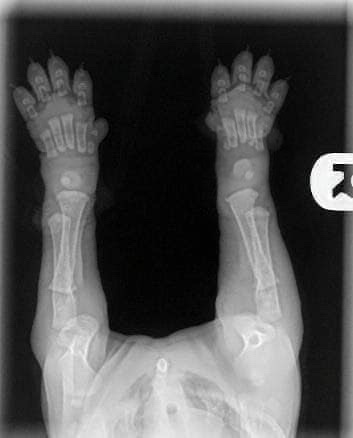

Когда вы получаете своих щенков в возрасте 8/12недель, пожалуйста, помните об этих фотографиях.

Видите их кости далеко друг от друга и даже нет намёка на соприкосновение. Вы заметили что все щенки, любой породы с большими гибкими лапками и шаткими движениями, их суставы полностью состоят из мышц, сухожилий, связок, покрытые сверху кожным покровом. Кости не могут плотно прилегать друг к другу пока не имеют настоящего гнезда - т.е. сформированного сустава. И чтоб защитить кости щенка от деформации.

ниже фото лап взрослой собаки